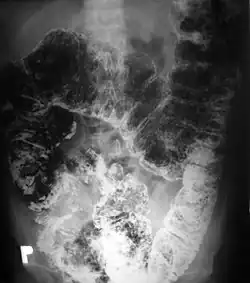

Polipowatość jelita grubego

Występowanie licznych polipów gruczolakowatych w jelicie grubym jest charakterystyczne dla zespołu rodzinnej polipowatości gruczolakowatej (znanej też jako gruczolakowatość rodzinna jelita grubego lub polipowatość rodzinna). Rozpoznaje się ją jeśli liczba rozrostów o charakterze polipa przekracza 100 w całym jelicie. Jest to genetycznie uwarunkowany zespół, predysponujący do występowania raka jelita grubego (100% nieleczonych chorych w ciągu 20 lat). Innymi nowotworowymi polipowatościami jelita grubego są: zespół Turcota, zespół Gardnera, zespół Oldfielda, zespół Zanca.